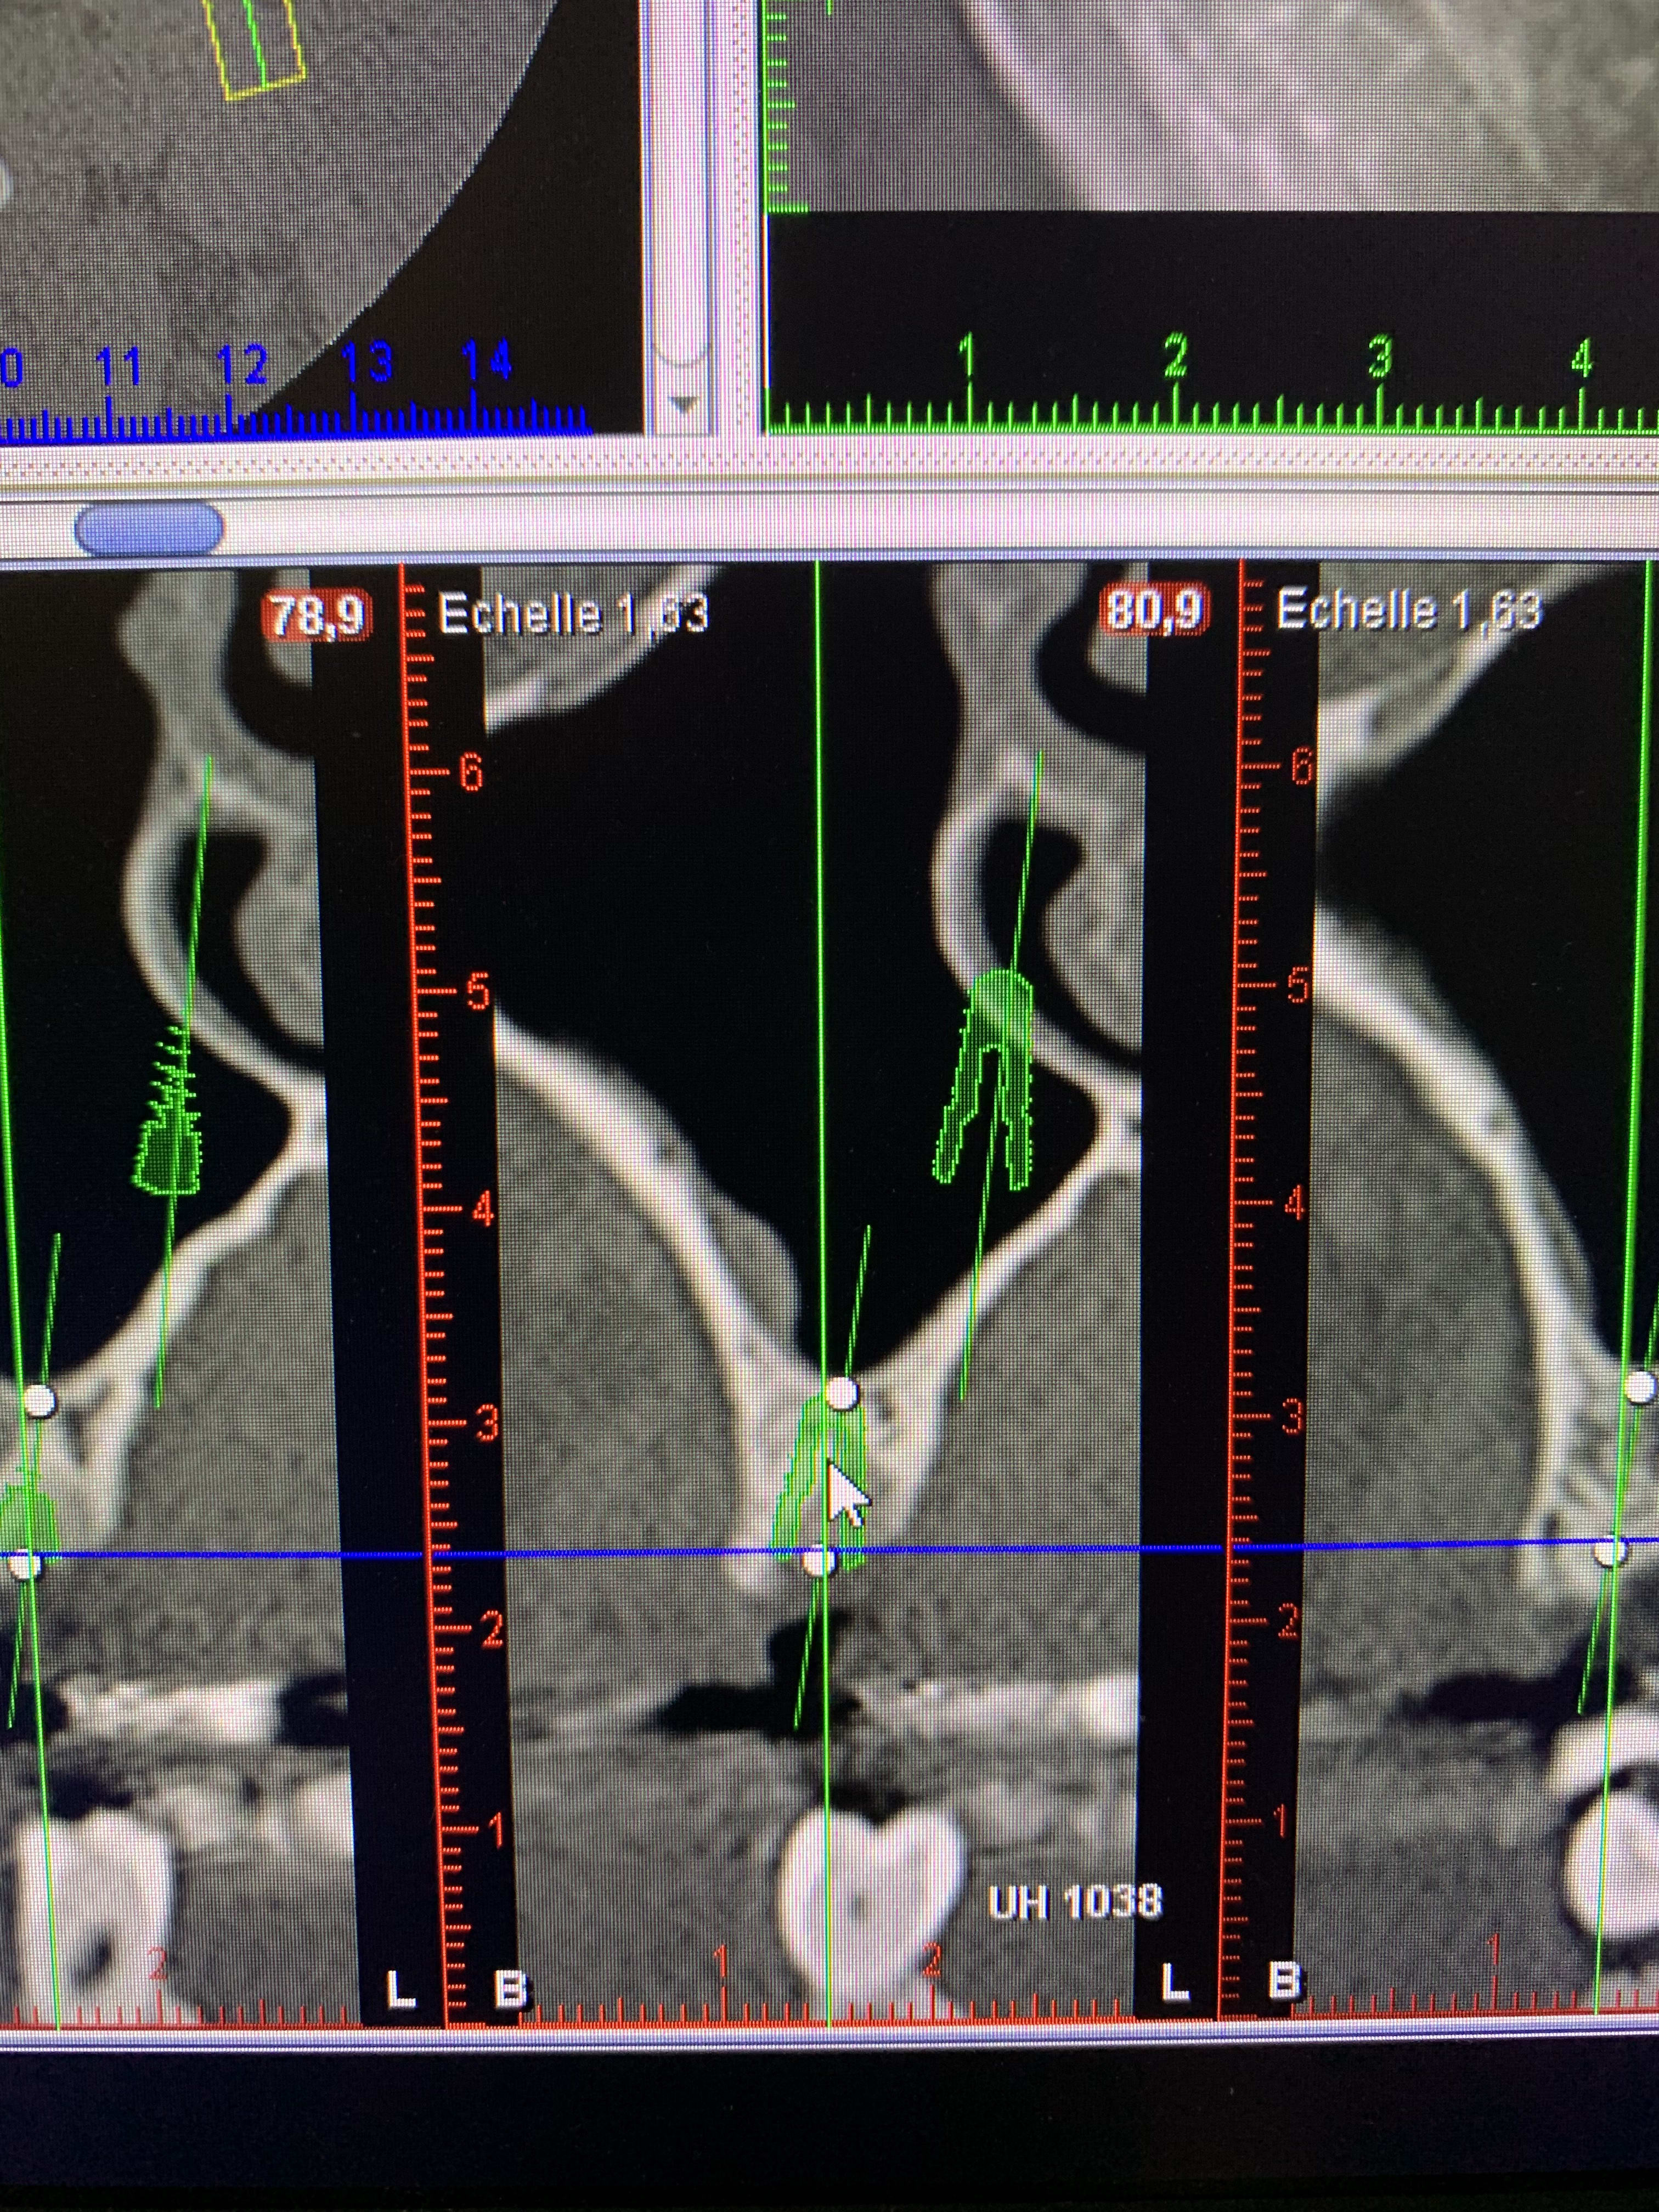

Merci ...oui l’implant est enfoui. L’ecoulement est jaune claire limpide. La gencive a eut du mal a se refermer et aujourd hui on voit une espece de manchon gingival mou dessus. Aucune douleur. Legere perte osseuse mais pas en hauteur. C est plutot le Long de l’implant que j’observe un petit espace noir... a ton avis. Si je depose, je repose combien de temps apres et avec quel protocole ?

Malheureusement, la crete ne permet pas de poser un implant plus large. Je vois le patient dans 10 minutes et je ne suis pas encore au cabinet donc pas de radio pour le moment mais j’essaierai d’en poster une avec. Par contre je ne maîtrise pas les Mac et je ne sais pas comment sortir la radio, je prendrai une photo

Je ne comprends pas ce qu’il s’est passé. Je vous mets des photos. Je suis désolé je ne maîtrise pas trop l’outil informatique pour faire autrement mais elles sont aussi nettes que ce que j’ai à l’écran

Implant trop gros (quel diamètre?)

et court non?

+1 implant trop gros, peut-être une fracture ou ischémie du pan vestibulaire

Je veux bien croire qu’il soit trop gros mais je ne comprends pas pourquoi vous avez vu l’épaisseur ou ce qu’il reste de chaque côté de l’implant sur le scanner ?

Ton implant est trop gros et pas assez long

Un 4/10 aurait été bien plus adapté

Tu as dû avoir une ischemie de la paroi vestibulaire